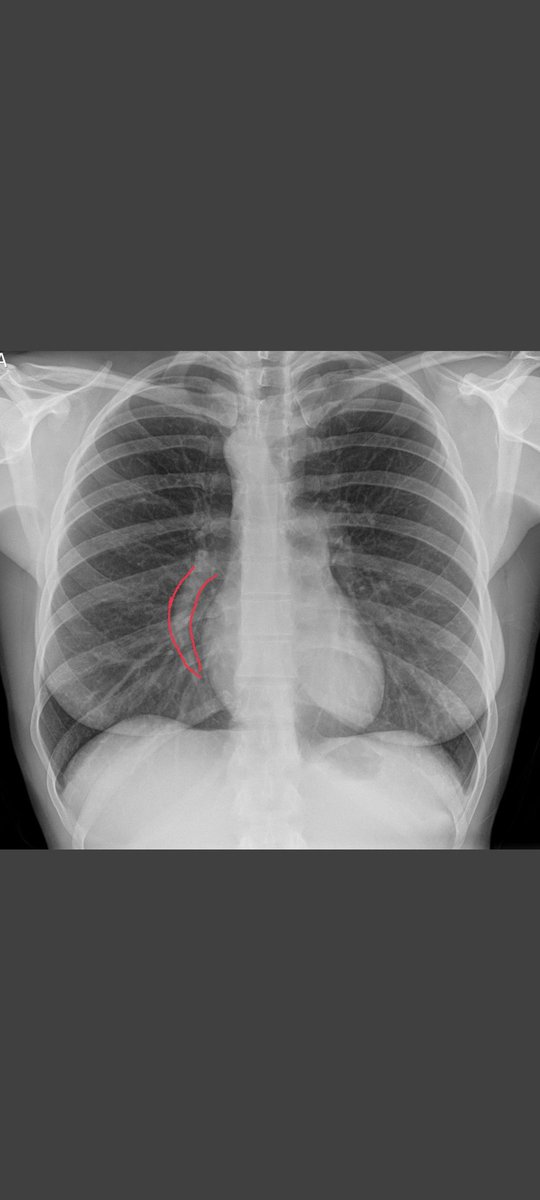

4D flow cat. If you know, you know. Product of the 3D Cardiac Vis Lab #SCMR23 @AlsaiedTarek @Kfarooqi @DrJenniferCo_Vu @LokeCmr

Co-director of Cardiac MRI Children's Hospital Colorado, Director of Clinical Informatics for the Heart Institute,